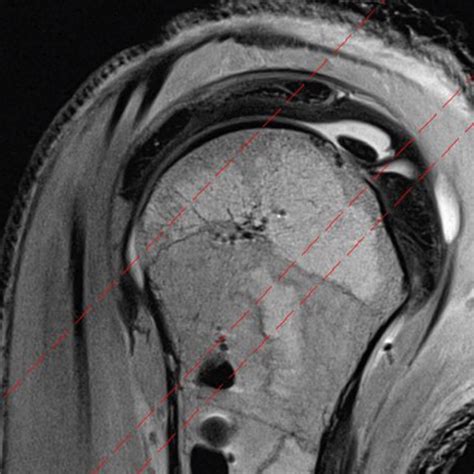

Accurately diagnosing conditions affecting the rotator cuff interval requires a combination of physical examination and advanced imaging. Physicians typically begin with clinical tests to isolate the function of the biceps tendon and the rotator cuff muscles. However, because the interval is deep, imaging is vital for a definitive diagnosis.

Magnetic Resonance Imaging (MRI) The gold standard for visualizing soft tissue, ligamentous thickening, and interval tears.